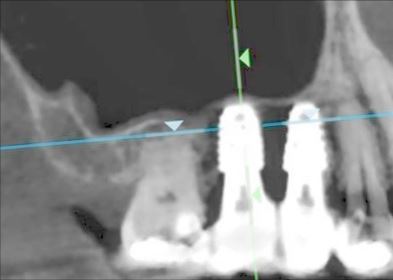

奥歯のインプラント症例⑥

治療前

治療後

治療内容

以前抜歯した部分にインプラントを入れました。副鼻腔粘膜を挙上して骨再生をしています。

期間 4か月

費用 税込90万円

起こりうる副作用・リスク 保険外治療です。

手術後にインプラントの定期メンテナンスを怠ってしまうと、インプラント周囲炎になるリスクが高まります。